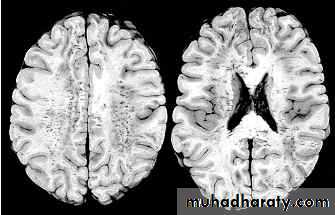

1. Diffuse Axonal Injury

Prolonged post-traumatic state in which there is loss of consciousness from the time of injury that continues beyond 6 hours.Occurs as a result of mechanical shearing at the grey-white matter interface.

This causes disruption and tearing of axons, myelin sheaths and blood capillaries.

Severity can range from mild damage with confusion to coma and even death.